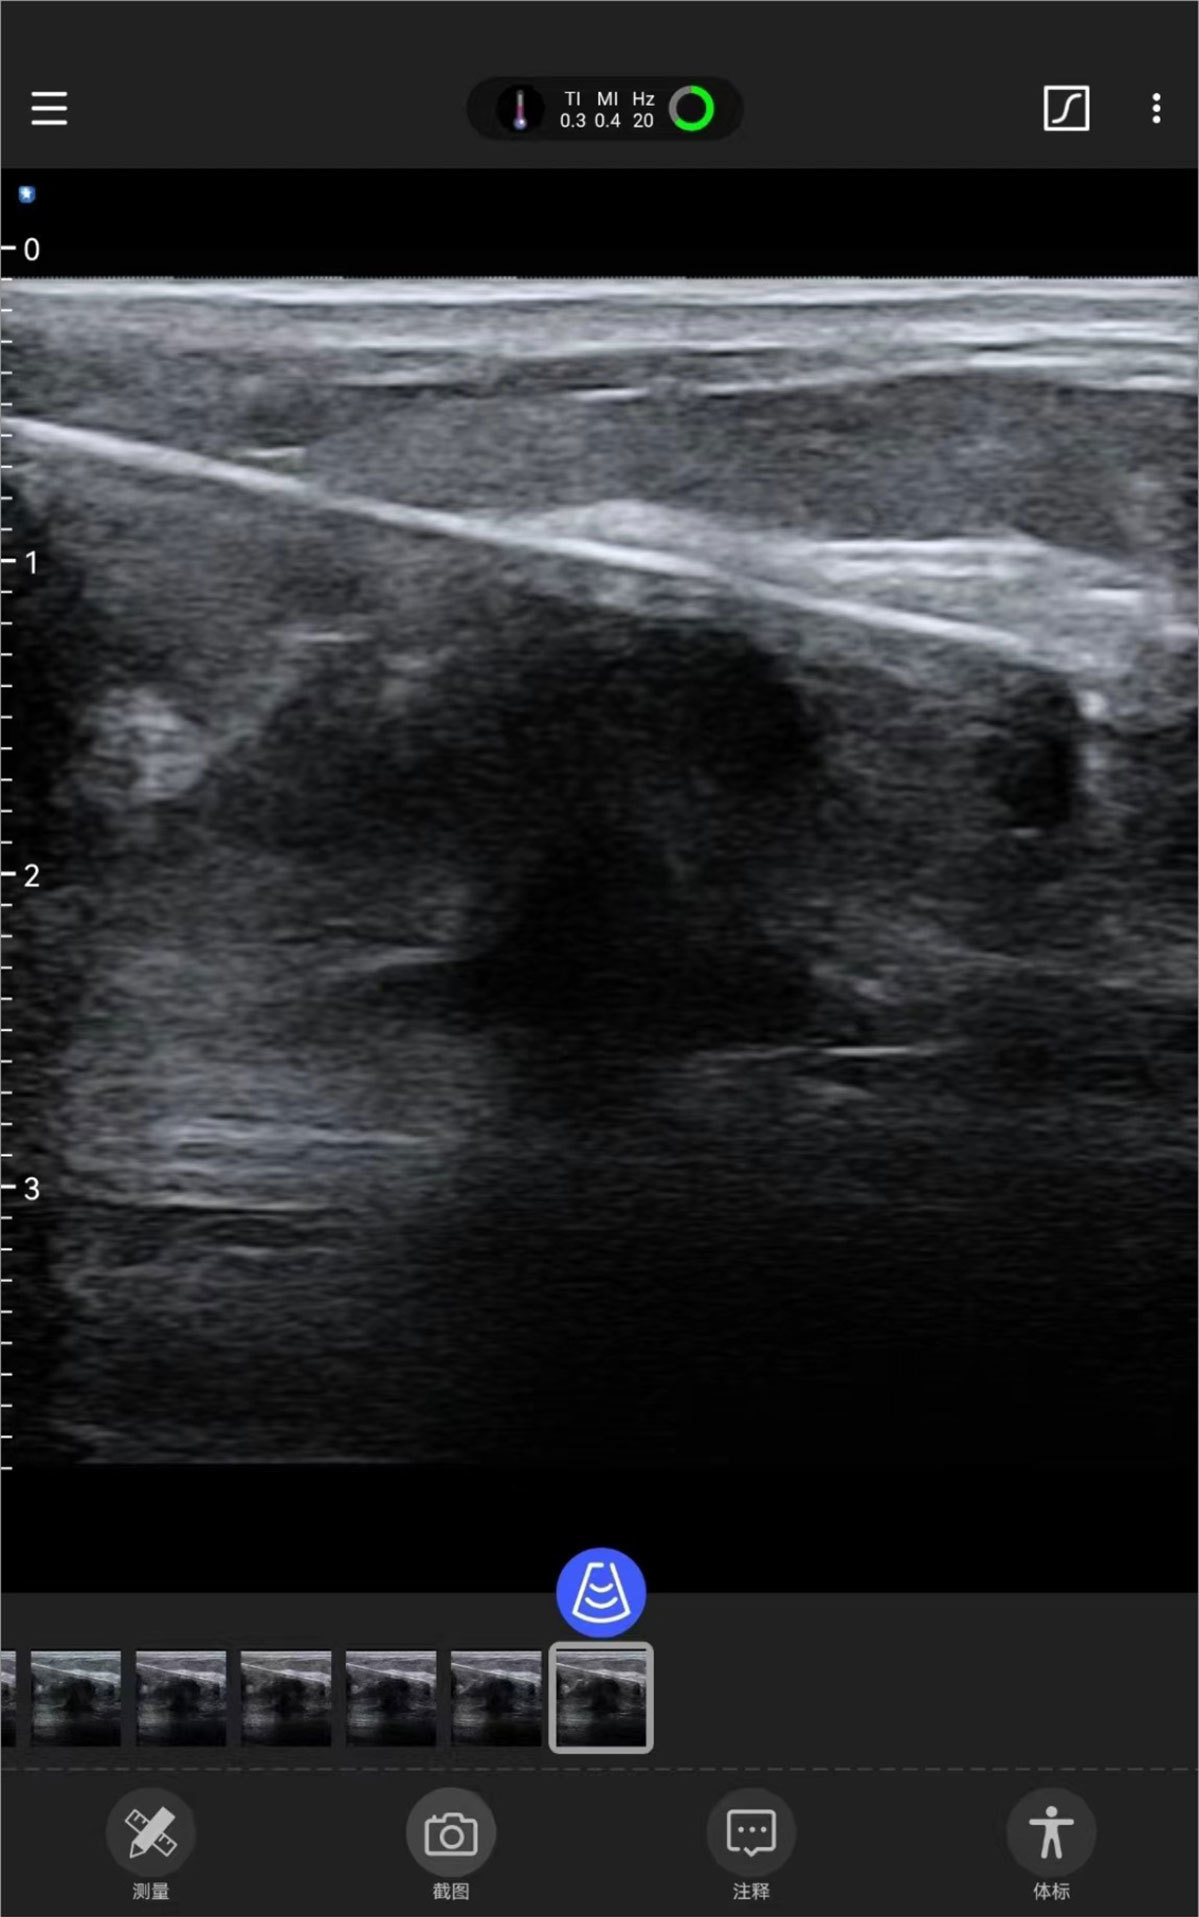

Tiroides Mama ( Guía de ablación por punción )

Galería de demostración